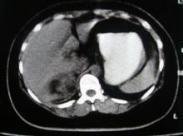

腹膜后脂肪瘤亦稱為原發性腹膜后脂肪瘤,腎臟或原發性腹膜后腹源臟器外脂肪瘤,即不包括發生在腎臟、腎上腺、胰腺等實質性臟器的脂肪瘤。早期常無癥狀,瘤體生長到相當程度才出現癥狀。